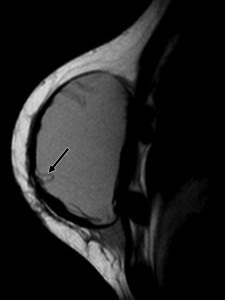

Para identificar y tratar rápidamente este problema antes de que se convierta en un riesgo para la salud, la FDA recomienda que las mujeres con implantes de silicona se sometan a pruebas de detección de fugas cada dos años.

Los funcionarios inicialmente recomendaron que esto se hiciera usando MRI.

Si bien esta estrategia fue ciertamente efectiva para identificar la ruptura del implante mamario, muchas mujeres no siguieron la recomendación.

No solo era costoso, hasta $2,000 de su bolsillo por cada resonancia magnética, sino que para algunas mujeres, las resonancias magnéticas también eran una fuente de ansiedad, dice el Dr. Pusic.

La FDA ahora recomienda una alternativa más fácil y económica: los exámenes de ultrasonido.

El ultrasonido se puede usar para la vigilancia de rutina y los problemas potenciales, confirmados mediante resonancia magnética.